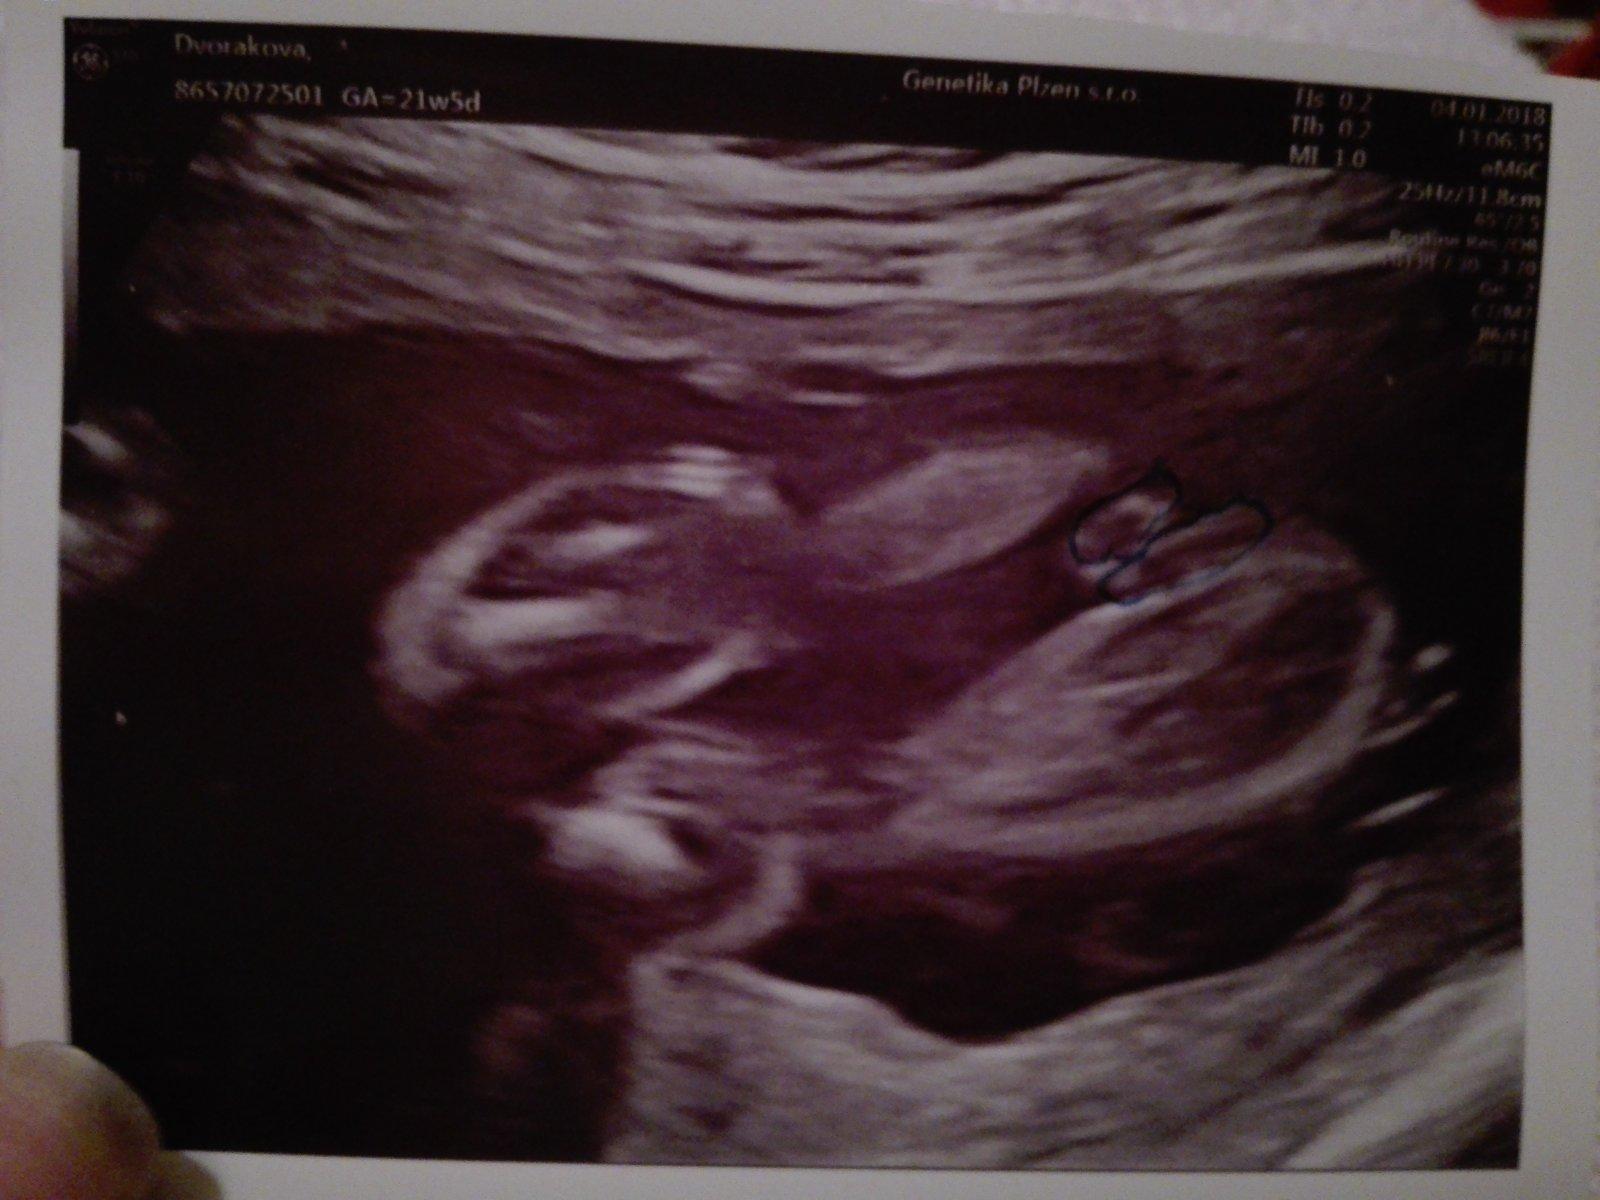

Ahoj maminky a budoucí maminky 😉 Prosím, poradila byste mi některá, co vidíte na fotce z ultrazvuku ve 20. týdnu za pohlaví? Určitě jste foteček viděly už mraky, proto vás žádám o radu...Nechci nikoho ovlivnit, proto svůj tip řeknu později 🙂 Děkuju moc!!!

@linee byla jsem minuly tyden 21+0 tt a doktor me vytocil...rikal,ze je to na ueceni jeste brzy a musim.si pockat 😡 mel blbou naladu a plnou cekarnu pupkatych mamin co cekaly na ultrazvuk...objednala jsem.se do Plzne na genetiku a 3D ultrazvuk...takte 13.12.uz snad budu vedet a pisnu jestli holka nebo kluk 😉

@mariejosef Díky za tip, já pořád přemýšlím, zda to jsou kulky či kávové zrno... pindíka jsem tam vysloveně na videu (mám nahrané) neviděla, ale určitě hodně závisí na úhlu... v 21t pořád netuším, co to bude (moji doktoři nejsou sdílní, když nevidí peníze) 🙂